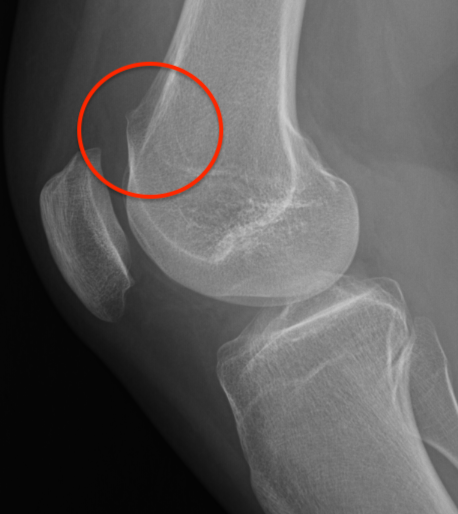

Bony MPFL avulsion

Patella subluxation

Patella should be well engaged in groove

Central ridge should lie at or medial to bisector of the trochlea groove

Patella well engaged in groove versus laterally subluxed patella